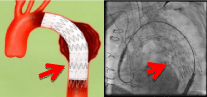

●ステント留置術

ステントという⾦属製で網⽬状の筒を⾎管内の狭窄病変に留置し狭窄の改善を図り、また動脈瘤部位に留置することで瘤の破裂を予防します。